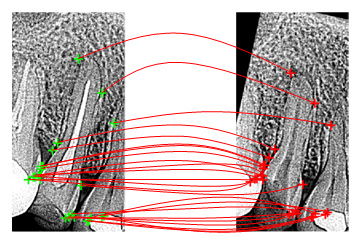

しかし、これまで、エックス線画像の照合は人手によって行われており、コンピュータによる自動照合は困難でした。これに対して、私たちのグループでは、「位相限定相関法」と呼ぶ超高精度画像マッチング技術に基づいて、エックス線画像に含まれるひずみを高精度に補正しながら自動照合する手法を提案しています(図2)。これは、画像の膨大な情報量を活用した、より精密な第二段階のスクリーニングの可能性を初めて示したものです。実際には、①の歯科所見や治療記録と②の歯科エックス線画像を複合的に用いることで、高度な身元検索が実現できると期待されます。

図2 位相限定相関法に基づく超高精度エックス線画像照合